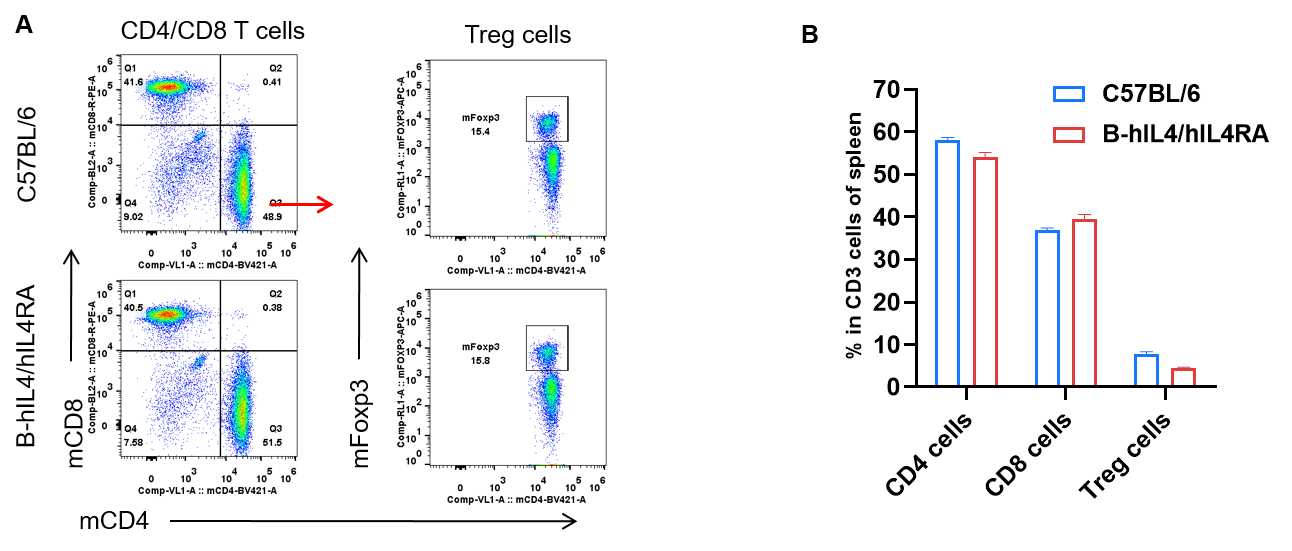

Analysis of spleen T cell subpopulations by FACS. Splenocytes were isolated from female C57BL/6 and B-hIL4/hIL4RA mice (n=3, 10-week-old). Flow cytometry analysis of the splenocytes was performed to assess leukocyte subpopulations. A. Representative FACS plots. Single live CD45+ T cells were gated for CD3+ T cell population and used for further analysis as indicated here. B. Results of FACS analysis. Percent of CD4, CD8, and Treg cells in homozygous B-hIL4/hIL4RA mice were similar to those in the C57BL/6 mice, demonstrating that introduction of hIL4 and hIL4RA in place of its mouse counterpart does not change the overall development, differentiation or distribution of these T cell sub types in spleen. Values are expressed as mean ± SEM.